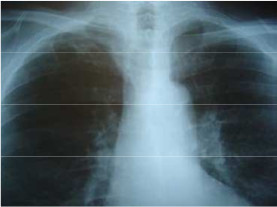

- Varón de 60 años que acude a urgencias por hemoptisis, febrícula y síndrome constitucional. Fumador de 20 cigarrillos al día desde los 18 años (42 paqetes/años); Bebedor de 100 g de etanol al día; Enfermedad actual: desde hace varios meses refiere astenia, anorexia y pérdida de más de 10 kg de peso, y desde hace 4-5 días presenta también disnea mayor de la habitual, siendo en la actualidad de mínimos esfuerzos, hemoptisis y febrícula, por lo que decide acudir a urgencias. Refiere desde hace años ronquido intenso con somnolencia diurna en inactividad. Exploración física: FC 90, FR 24, Tª 37.5, TA 140/94, índice de masa corporal 32 kg/m². Consciente, orientado, taquipneico, con sobrepeso y con aspecto higiénico descuidado. Dentadura en mal estado general y ligero olor enólico. Rítmico sin soplos cardíacos. Roncus y sibilancias bibasales. Abdomen y extremidades normales.

Indique:

- Posible DX.

- Posible TTo.

- Explique que se visualiza en la RX tórax.